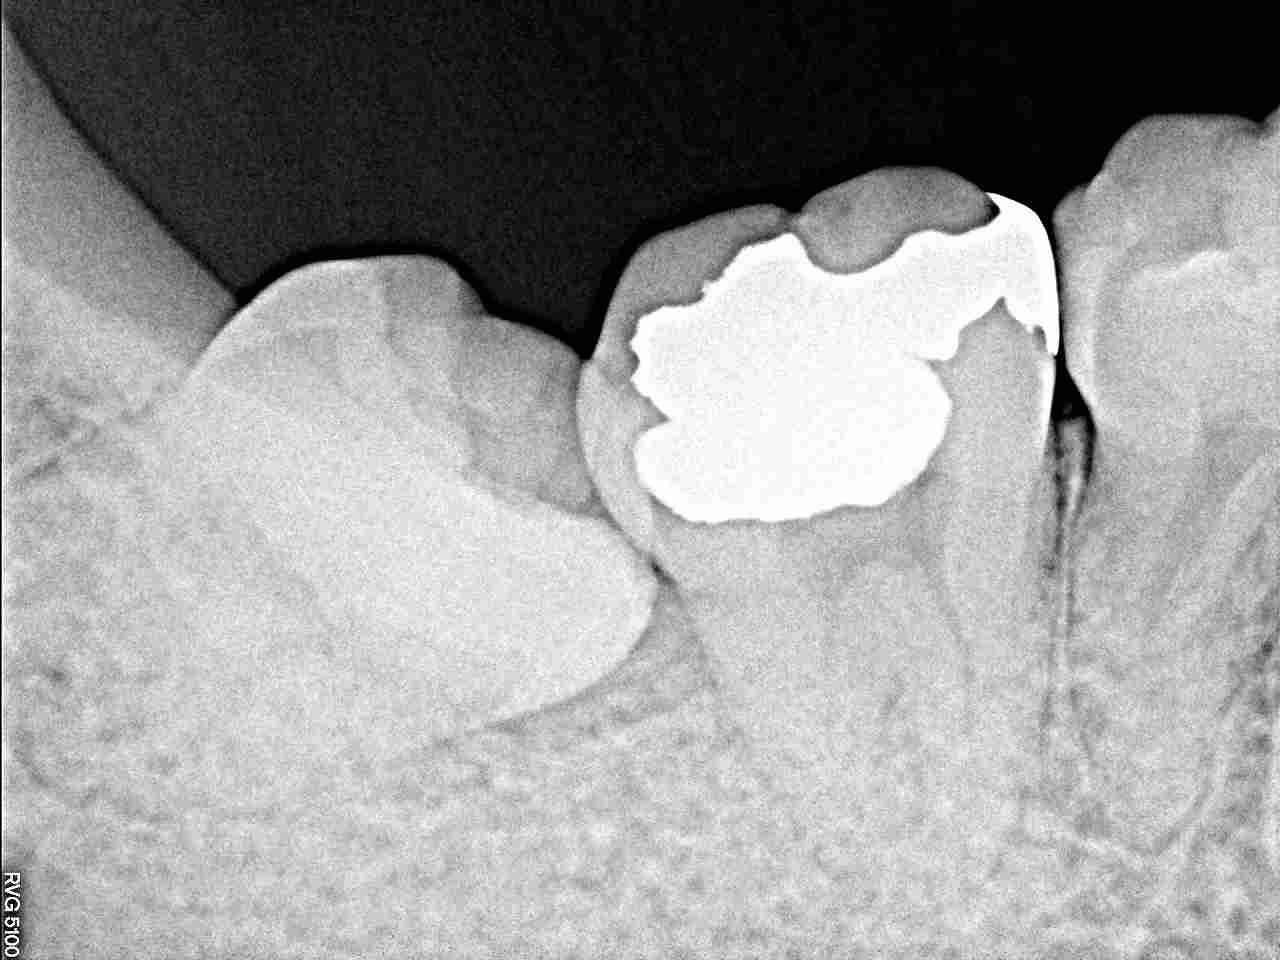

右下、簡単な親知らずになります

それでもレントゲンからも、横に埋まっています

抜歯して縫合です

15分もあれば、すべてが終わります